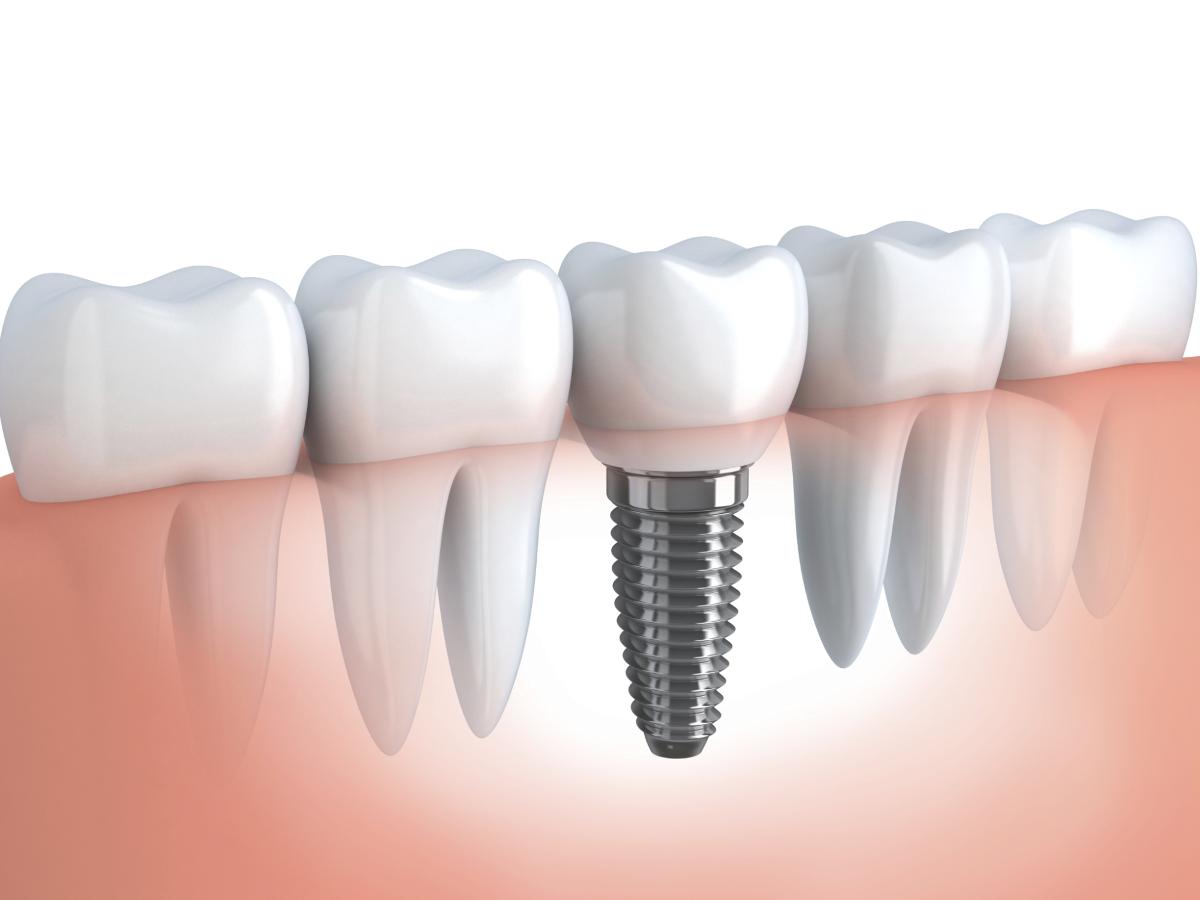

Современная стоматология в городе Сумы предлагает два вида протезирования зубов: съемные, несъемные конструкции.

Если отсутствует большое количество зубов, то протезирование может происходить несколькими способами. Современные способы позволяют решить данный вопрос, пациент никакого дискомфорта не будет испытывать. Современные ортопедические конструкции создают с применением самых новых материалов, а также технологий.